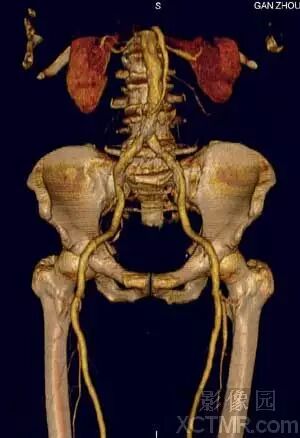

2)血管系统

VR作为MS-CTA的主要后处理技术在血管系统特别是对动脉血管系统病变要以清晰、确切地显示大范围复杂血管的完整形态、走行和病变,图像立体感强,能以多角度直观地显示病变与血管、血管之间以及血管与周围其它器官之间的三维空间解剖关系,其诊断价值已经被临床医生认可。对大动脉血管病变如:动脉瘤、动静脉畸形、狭窄、梗塞、闭塞、夹层和血管壁的钙化等的诊断已经基本取代了DSA检查。对脑动脉瘤的诊断国、内外有关研究报告证实3D-CTA具有很高的准确性、敏感性和特异性,可以确切地检出瘤体直径<3mm的脑动脉瘤。作为一种快速和非创伤性检查手段,可以准确地显示瘤体的位置、形态和大小,评价瘤颈部与瘤体、载瘤动脉和周围血管之间的空间关系,模拟手术入路为选择适当的手术治疗方案提供直观、可靠的依据,可以作为脑动脉瘤的首选影像学诊断方法。近年来,有许多文献报道主张用3D-CTA取代或部分取代DSA诊断脑动脉瘤。